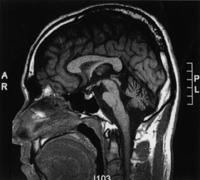

60歳の男性。7年前から歩行時にふらつきを自覚し、6年前から話し方が単調で途切れ途切れとなり膀胱直腸障害と起立性低血圧を認めた。四肢の固縮や振戦が徐々に進行し、2年前から車椅子で移動するようになった。最近、声が小さくなり呼吸困難感を訴えるようになった。頭部MRIのFLAIR画像で水平断(A)および矢状断(B)を示す。この疾患で合併する可能性が高いのはどれか。

1

失 語

2

拮抗失行

3

声帯麻痺

4

下方注視麻痺

5

他人の手徴候